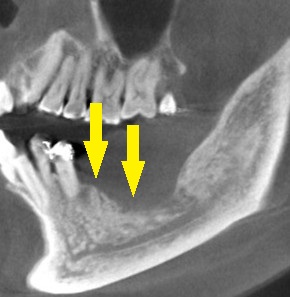

3か月ほどして、CTを撮影してみると、下の写真2段目のように、大きく骨欠損となっていました。

2本のインプラント埋入を目指したいのですが、2本目の部位では、下方に通っている神経までの距離は3~4mm程度でした。

ショートインプラントでも厳しいので、この場合は、人工骨を用いて、上方に骨を増やす手術を併用する計画としました。